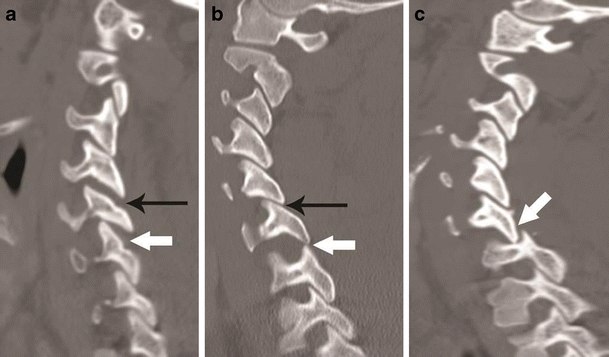

Facet joint injury spectrum resulting from hyperflexion distraction. Parasagittal CT images. a The C4–C5 facet joint shows diffuse widening—diastasis (black arrow), and the C5–C6 facet joint shows focal anterior widening (white arrow), suggestive of distraction injury and partial disruption of facet joint capsule. Articular surfaces are congruent and no uncovering of the inferior articular process noted at any of the injured levels. b C5–C6 facet joint subluxation (black arrow), suggested by non-congruent articular surfaces of the facet joint with anterosuperior displacement of the inferior articular process of C5, resulting in partial uncovering of the superior articular surface of C6. However, some apposition of articular surface is still intact. C6–C7 facet joint dislocation (white arrow) suggested by anterior and superior translation of inferior articular process of C6 resting on the top of the C7 articular process, resulting in complete loss of articular apposition and uncovering of C7 articular facet. A facet joint injury as seen at C6–C7 is also named as a “perched facet”. c C6–C7 facet joint dislocation with further anterior translation of the inferior articular process (white arrow), now resting anterior to the C7 articular pillar. This injury is also called a “locked” or “jumped facet”